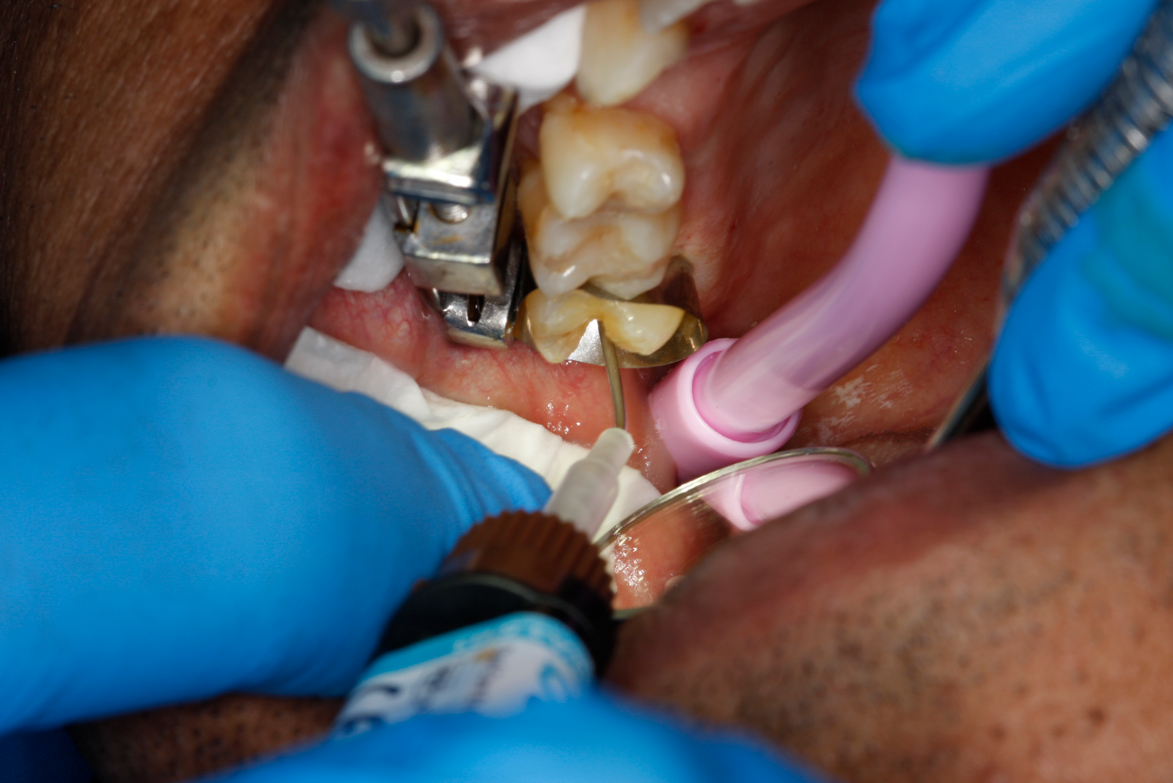

Fig 32. Preparation is completed, caries are removed, sand blasting with potassium carbonate is performed, and matrix band is placed.

Figure 32

Fig 33. Total etch with 37% phosphoric acid is performed.

Figure 33

A deep distal occlusal preparation was performed and a matrix band (Paraband, Practicon) was placed again, such that no wedge needed to be placed (Figure 32). The Groman Etchmaster was utilized to remove biofilm as previously shown in Figure 12. A total etch technique with 37% phosphoric acid was employed (Figure 33), and after thorough rinse and damp dry, a universal adhesive (Scotchbond Universal, 3M) with MDP was applied and light-cured 40 seconds at 1,200 mw/cm2 due to the depth of the box form (Fig- ure 34). Figure 35 shows the dual-cure bulk-fill flowable composite (Bulk EZ Plus, Zest Dental Solutions) being injected into the deep box with a 20-gauge bendable needle. It is important to keep extrusion pressure on the plunger while withdrawing the needle to prevent bubbles or voids in the composite interface with the tooth structure. Overfilling by approximately 10% and smoothing the surface only with brushes promotes good marginal seal (Fig- ure 36). It is critical to not disturb the occlusal surface of any dual-cure bulk-fill flowable with an attempt to "soft sculpt," as that may create marginal voids.